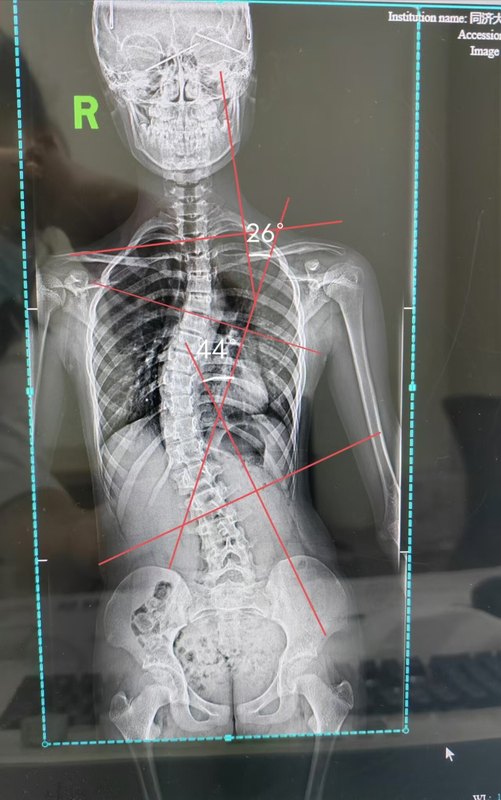

脊柱側(cè)彎矯正我們是認真的,接近40度的大彎撲面而來,當(dāng)我拍胸脯的那瞬間,不僅是自信,更是對于我們團隊技術(shù)的認可。?這一年,我們不斷地在推崇四維一體化的脊柱側(cè)彎矯正,不僅僅只是支具,不僅僅只是治療。融合,在合適的條件下進行選擇,真的非常非常重!當(dāng)然不得不提的就是服務(wù),每一個家長幾千公里帶著孩子來到我的面前,我們又有什么理由不認真?我們又有什么理由不努力?我們更有什么理由不做好服務(wù)?希望小女孩今晚在外灘玩得開心~側(cè)彎的路上,我們陪你共同成長,加油!